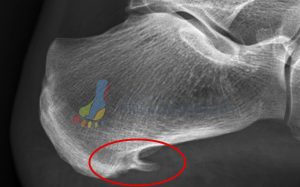

The Calf Muscle Attachment (Posterior Heel Spur):

- The number one muscle that is tight in at least 95% (anecdotal figure) of patients is the calf muscle. As a result on imaging we can typically see spurring, or at least excess bone deposit at the rear of the heel where your achilles tendon attaches to the heel bone. You can find an example of this shown on the foot x-ray below highlighted by the red circle.

The Arch Muscle Attachment (Plantar Heel Spur):

- the next common muscles that are tight in many patients experiencing heel pain are the arch muscles. Please be aware there are multiple arch muscles in the foot – here we’re over-simplifying the topic for ease of illustration but many share a similar attachment point at the bottom of the heel bone. You can find an example of this shown on the foot x-ray below highlighted by the red circle.

The Arch Ligament Attachment (Plantar Fascial Heel Spur):

- the final point that is rarely seen by itself but still worth a mention as it is a sign of long-standing plantar fascia attachment irritation of the heel bone is what we call the plantar fascial heel spur. This attachment point is the true attachment of the plantar fascia and irritation here is a sign of excessive strain through the plantar fascia. Bear in mind your plantar fascia is a strong ligament (bone to bone not muscle to bone with a tendon) so when this is pulling excessively your foot muscles have ‘given up’. You can find an example of this shown on the foot x-ray below highlighted by the arrow pointing at the red circle.